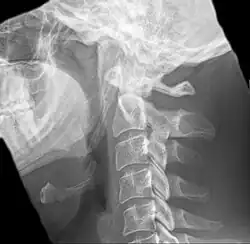

Anteroposterior and lateral radiographs of cervical spine showing ossification of the stylohyoid ligament on both sides

Imaging is important and is diagnostic. Visualizing the styloid process on a CT scan with 3D reconstruction is the suggested imaging technique.[13] The enlarged styloid may be visible on an orthopantogram or a lateral soft tissue X ray of the neck.